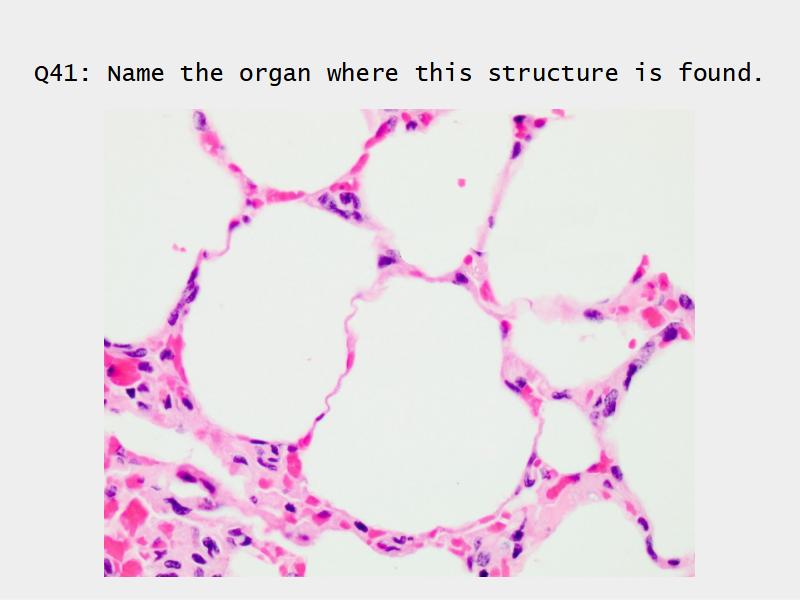

- Slide 72 & 74: Lung

- Alveoli

Lungs